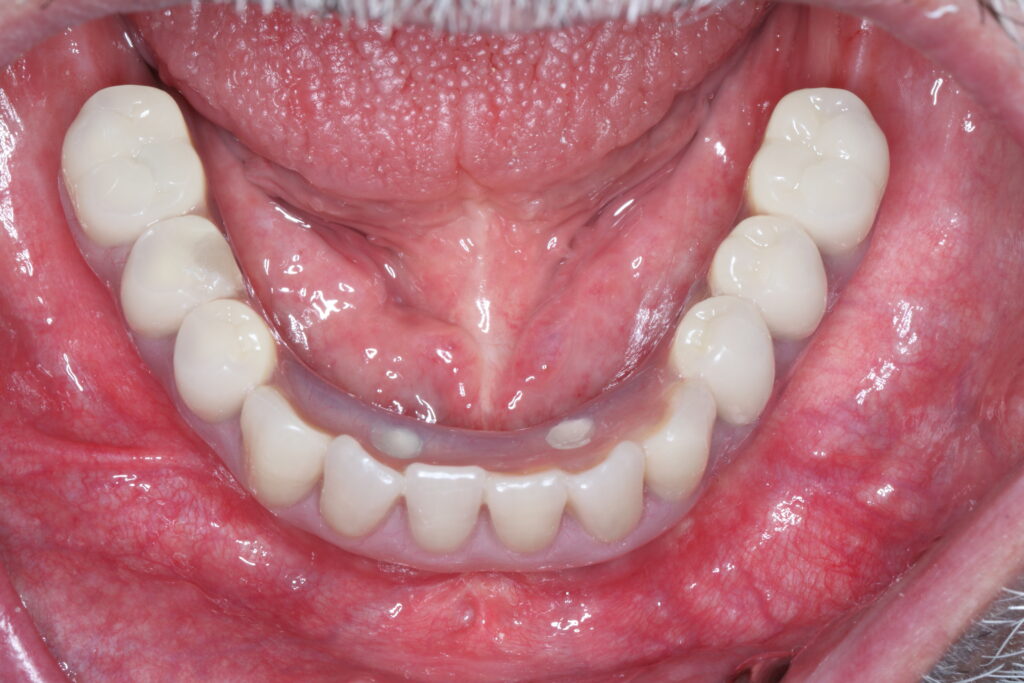

A selection of full arch fixed implant bridge patients after 5 years of wear

Oral Surgeons – Dr Han Choi, Dr Sam Goldsmith, Dr Rajiv Rajpal NSOMS

Prosthodontist – Dr Alan Payne NSOMS/Northland Prosthodontics

Dental technicians – Hosaka Takashi, DT Denture Design, Auckland, CJ Park, Project Dentistry, Auckland and Osteon Medical, Melbourne, Australia.